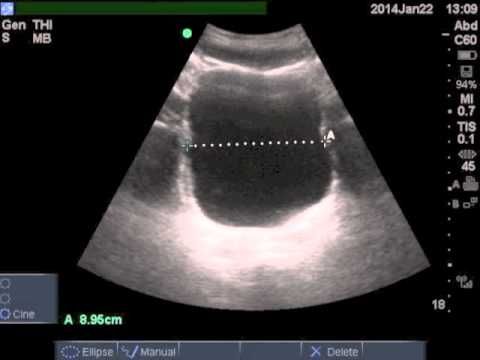

- УЗИ пузыря и органов малого таза. Такое исследование проводится в две фазы. Первая – при заполненном мочевом пузыре, чтобы измерить его объем и размер. Второе УЗИ – через 5-10 минут после его опорожнения. Чтобы результат был точный, расчеты проводятся минимум три раза. Есть специальные формулы для вычисления количества жидкости, для которых нужны следующие параметры:

- высота;

- ширина;

- длина УЗИ-тени пузыря.

Также определение ООМ проводят с помощью УЗИ. Его проводят дважды. Первый раз с полным пузырем, а затем за 5−10 минут после мочеиспускания. Определяют количество жидкости по специальной формуле. Во внимание берутся высота, ширина и длина пузыря. Для того, чтобы результат ООМ был точным, процедуру проводят 3 раза.

- Метод, который определит объем остаточной мочи в МП – абдоминальное УЗИ.